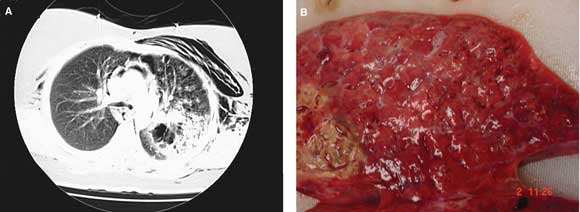

On presentation, the patient was in respiratory distress, with a respiratory rate of 36 per minute, pulse of 140 bpm, and oxygen saturation of 72% in room air. Subcutaneous emphysema was noted over the upper chest wall. Multiple healing and healed vesicles were present. The provisional clinical diagnosis was pneumonia, in the presence of resolving varicella. Results of blood tests on admission are shown in Box 1. Blood film demonstrated neutrophilia with toxic changes. Chest x-ray revealed pneumomediastinum and subcutaneous emphysema, while computed tomography showed pneumomediastinum and consolidation in the left upper lobe with cavitation (Box 2A). Electrocardiography revealed sinus tachycardia with paroxysmal atrial fibrillation.

Despite maximal support, the patient died 44 hours after presentation. An autopsy confined to the chest and abdomen showed interstitial emphysema involving the mediastinum, pericardium and left upper lobe of the lung, and extensive necrotising left bronchopneumonia with abscess formation, but no signs of pneumothorax (Box 2B). Numerous gram-positive cocci consistent with streptococci were evident on microscopy of lung sections. Varicella zoster virus DNA was detected by polymerase chain reaction in one of three tissue samples tested, but no viral cytopathic changes were seen, and no virus was detected by culture.

2 Appearance of the lungs in a patient with group A streptococcal pneumonia

A: Computed tomography of the chest on admission showed subcutaneous emphysema, pneumomediastinum and consolidation in the left upper lobe with cavitation. B: Postmortem examination showed extensive necrotising left bronchopneumonia with abscess formation.